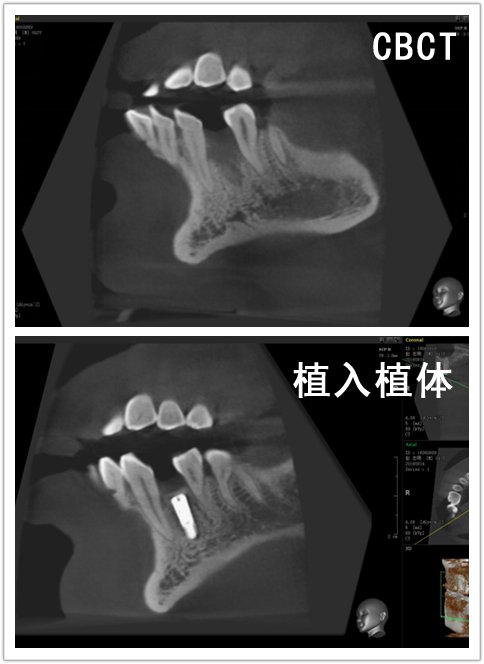

CBCT:34颊侧骨缺损。

治疗方案:34植骨+美格真种植修复。

治疗过程:34必兰局麻下,切开翻瓣,在生理盐水冷却下,先锋钻,扩孔钻逐级备洞,植入美格真4.0*11.5mm种植体一枚,颊侧植骨+GBR,严密缝合。